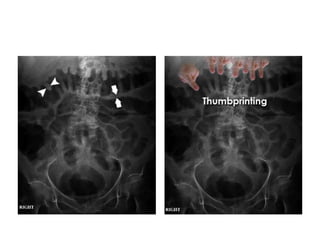

• Occasionally, abdominal X-rays show signs of

inflammation in patients with inflammatory

bowel disease. Abnormalities may relate to

either acute or chronic stages of disease.

• Mucosal thickening -

'thumbprinting'

• This patient presented with

an exacerbation of

symptoms of ulcerative

colitis .

• The distance between loops

of bowel is increased

(arrows) due to thickening

of the bowel wall. The

haustral folds are very thick

(arrowheads), leading to a

sign known as

'thumbprinting.'